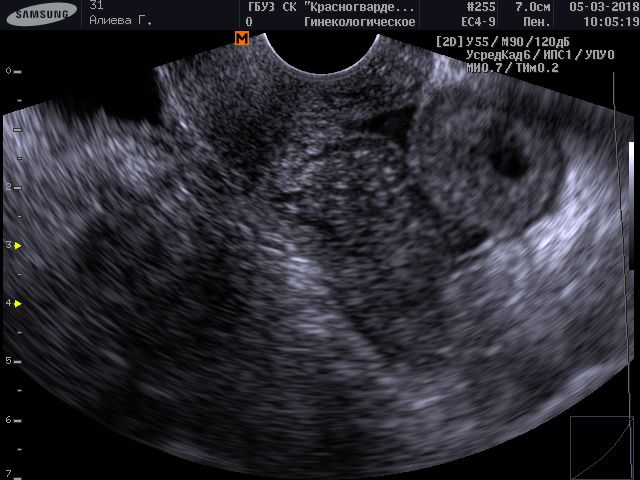

Эта ситуация одна из самых сложных в диагностическом плане . В матке обнаруживается плодное яйцо, но оно категорически не соответствует сроку, наблюдается существенное отставание роста .

Плодное яйцо образуется после слияния яйцеклетки и сперматозоида . Если оно расположено в матке, то можно говорить о маточной беременности . Если врач, который проводит ультразвуковое . . .

На 4 сутки эмбрион перемещается в полость матки, где продолжает делиться и увеличиваться в размере . На УЗИ плодное яйцо в матке можно увидеть только на 5 неделе .